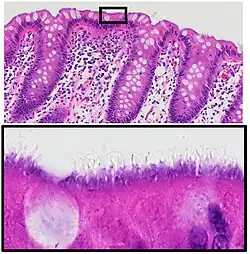

| Histopathology of intestinal spirochetosis, showing basophilic, fringe-like, end-on-end attachment of filamentous densely packed spirochetes on the surface epithelium of the intestinal mucosa.[1] H&E stain. | |

It is diagnosed by examination of tissue, i.e., biopsy. A hallmark finding is the presence of a “false brush border” on the luminal surface of the epithelium, formed by dense linear colonization of spirochetes.[4]

- ^ Image by Mikael Häggström, MD. Reference for description: Elliot Weisenberg, M.D. "Intestinal spirochetosis". Pathology Outlines. Last author update: 1 May 2017. Last staff update: 3 May 2022